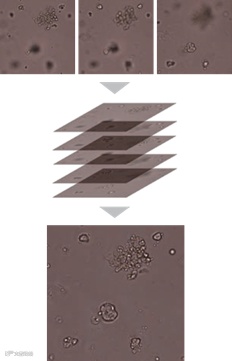

Z-Stack多层扫描:3D培养的类器官进行多层扫描,获取全焦点最佳图像

在Z轴方向上可进行Z-stack自动多层扫描,并自动进行图像处理合成一张全焦点清晰图像。